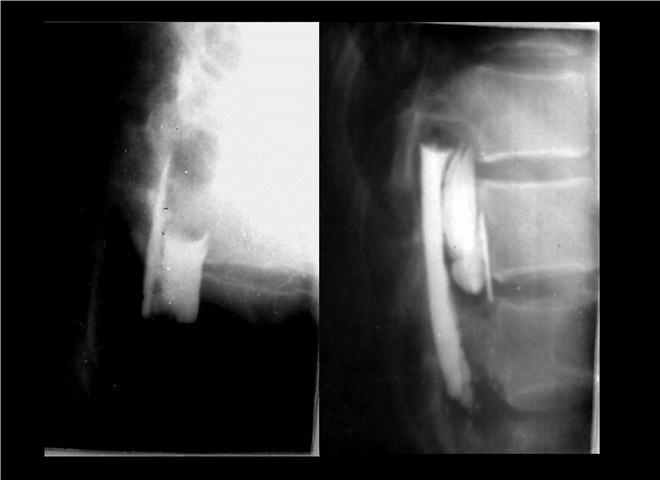

13_CT增强扫描